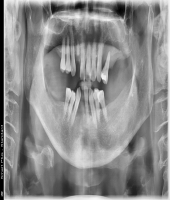

| ● 진료과목 : [임플란트] 치주환자의 보철치료

| ● 내용 : 60대 치주환자의 보철치료 |